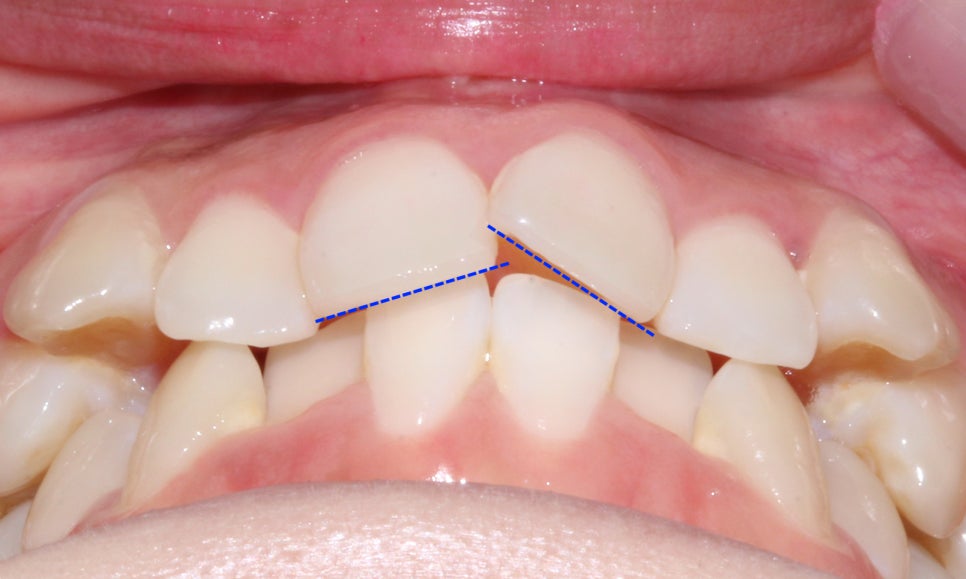

위의 overbite 사진에서도 송곳니덧니 증상으로

전치부의 치열이 심하게 삐뚤거리는 것을 확인할 수 있는데요,

좌우의 송곳니 위치가 좋지 않기 때문에

일반적인 부분교정 만으로는 스마일라인을

심미적으로 교정하기에는 무리가 있습니다.